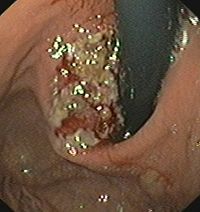

二.内腔镜检查:纤维食管镜或胃镜均可以作为诊断贲门癌的重要的检查方法。可以了解病灶发生的部位、长度、食管狭窄程度等的诊断。贲门癌没有明确确诊时应在短期内做内腔镜复查。